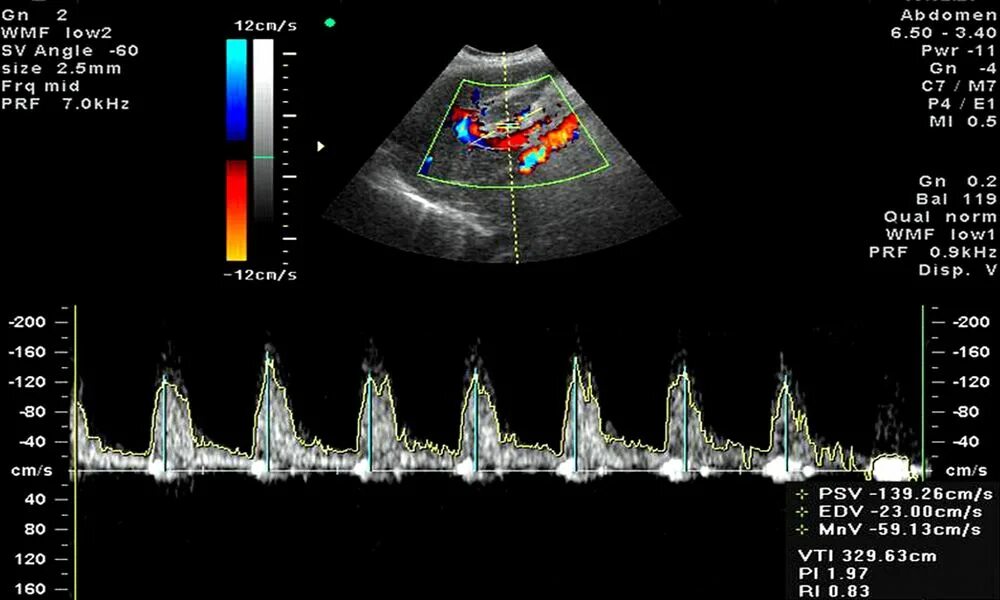

Доплер норма